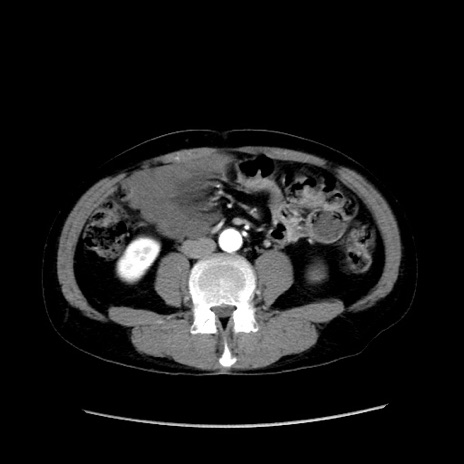

症例37(横断像)

【症例】40歳代 男性

【主訴】腹痛

【現病歴】4時間ほど前に電車に乗車中に臍部上より腹痛出現。徐々に増悪し起立困難となり、救急外来受診。生ものは数日食べていない。今朝お雑煮を食べた。

【身体所見】BT 36.8℃、BP 117/84mmHg、HR 91/min、SpO2 97%、苦悶様、腹部:臍上部広範囲圧痛あり、反跳痛±

【データ】WBC 8100、CRP 0.03